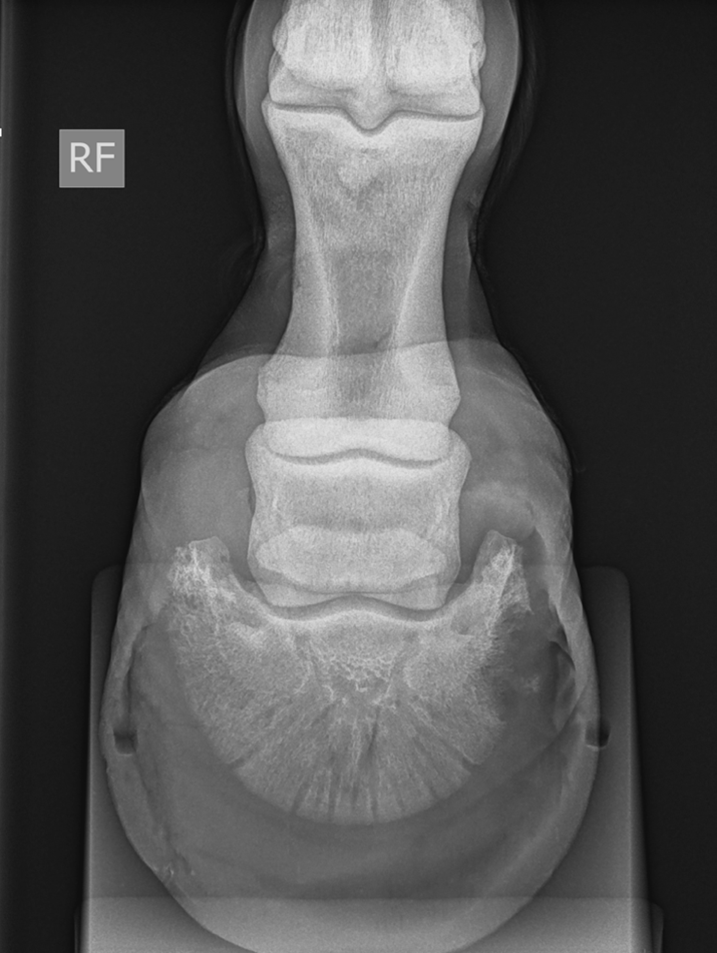

Volgende radiografische projecties (DPr-PaDiO en DMPr-PaLDiO) van de voet werd genomen.

- Groot en onregelmatig afgelijnd defect ter hoogte van de palmaromediale rand van het hoefbeen, over een dorsopalmaire afstand van circa 3 cm.

- Kleine, gemineraliseerde, onregelmatig en onscherpe opaciteit (ongeveer 6 mm) gesuperponeerd op het hoefkapsel en aangrenzend aan dit defect.

- Het hoefkapsel vertoont ter hoogte van deze regio een matig heterogeen aspect (gasopaciteiten en/of hoefdefect).